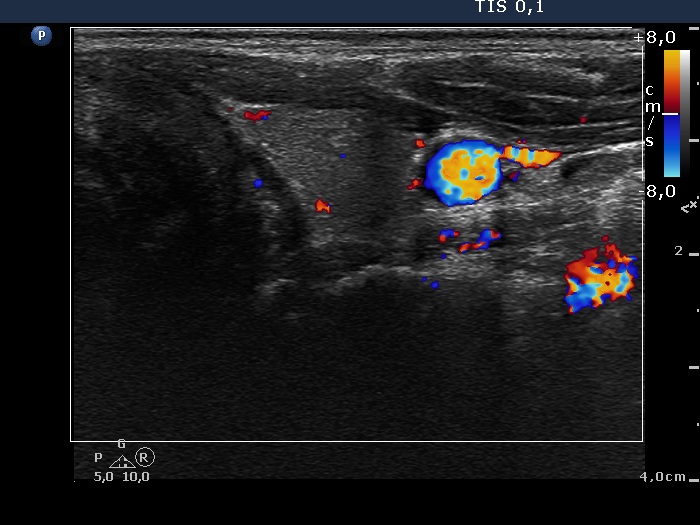

Differential diagnostic of thyroid cysts - Case 10. (ultrasonographic picture 7)

Left lobe, horizontal view, color Doppler mode. The vascularization is not specific.